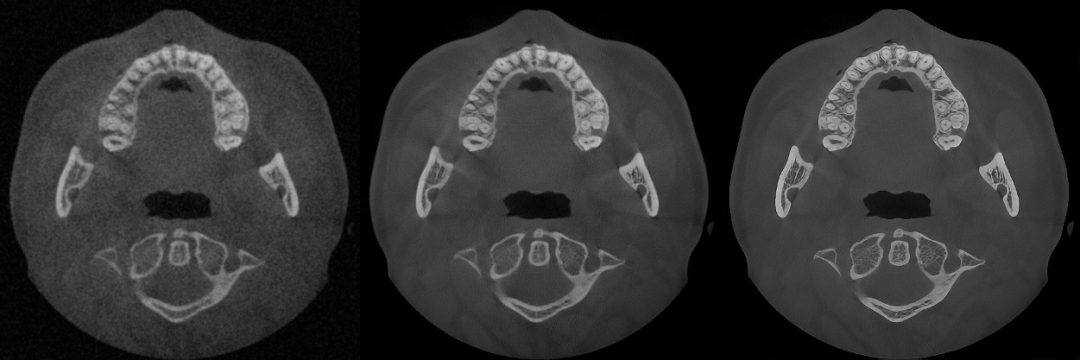

▲From left to right: Original Image, Mainstream Algorithm, "PD" Technology

▲Advantages of "PD" Technology: Deep Restoration of Image Details